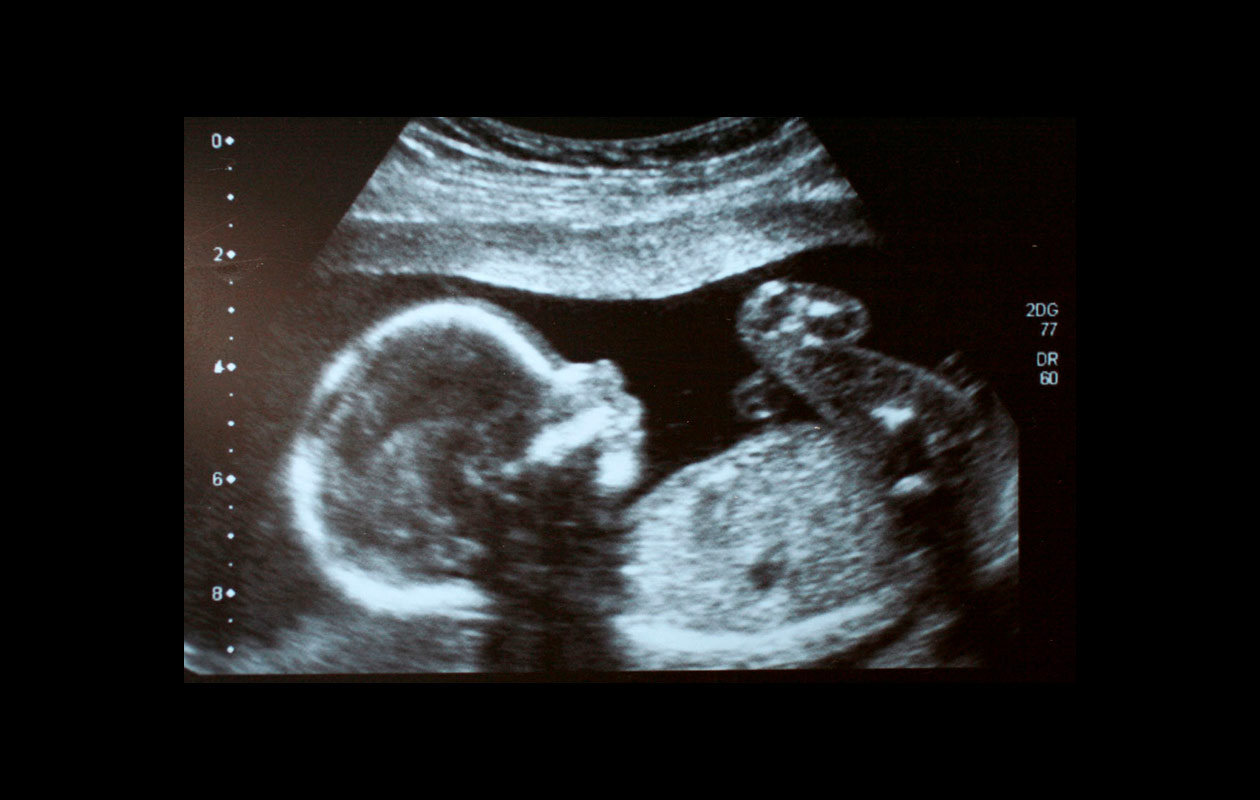

Teen ultraäänitutkimuksia kaikissa raskauden vaiheissa, myös jälkitarkastuksia.

Varhaisraskauden ultraäänitutkimus

Alkuraskauden ultraäänitutkimukset tehdään yleensä emättimen kautta.

Jos viimeiset kuukautiset ovat epäselviä, raskauden kesto on helppo tarkistaa kaikututkimuksella.

Sikiön syke on todettavissa 5.–6. raskausviikolta alkaen, mutta 5–10 %:ssa normaaleista raskauksista se nähdään hieman myöhemmin.

Ultraäänitutkimus on kivuton ja turvallinen äidille ja sikiölle.

Raskauden tilan ultraäänitutkimus (Yli 12 raskausviikot)

Yli 12 raskasviikoilla ultraäänitutkimus tehdään vatsanpeitteiden päältä, koska kohdussa oleva lapsivesi toimii sopivana kontrastina.

Tutkimuksessa tarkistetaan sikiön vointi, istukan toiminta ja lapsiveden määrä.